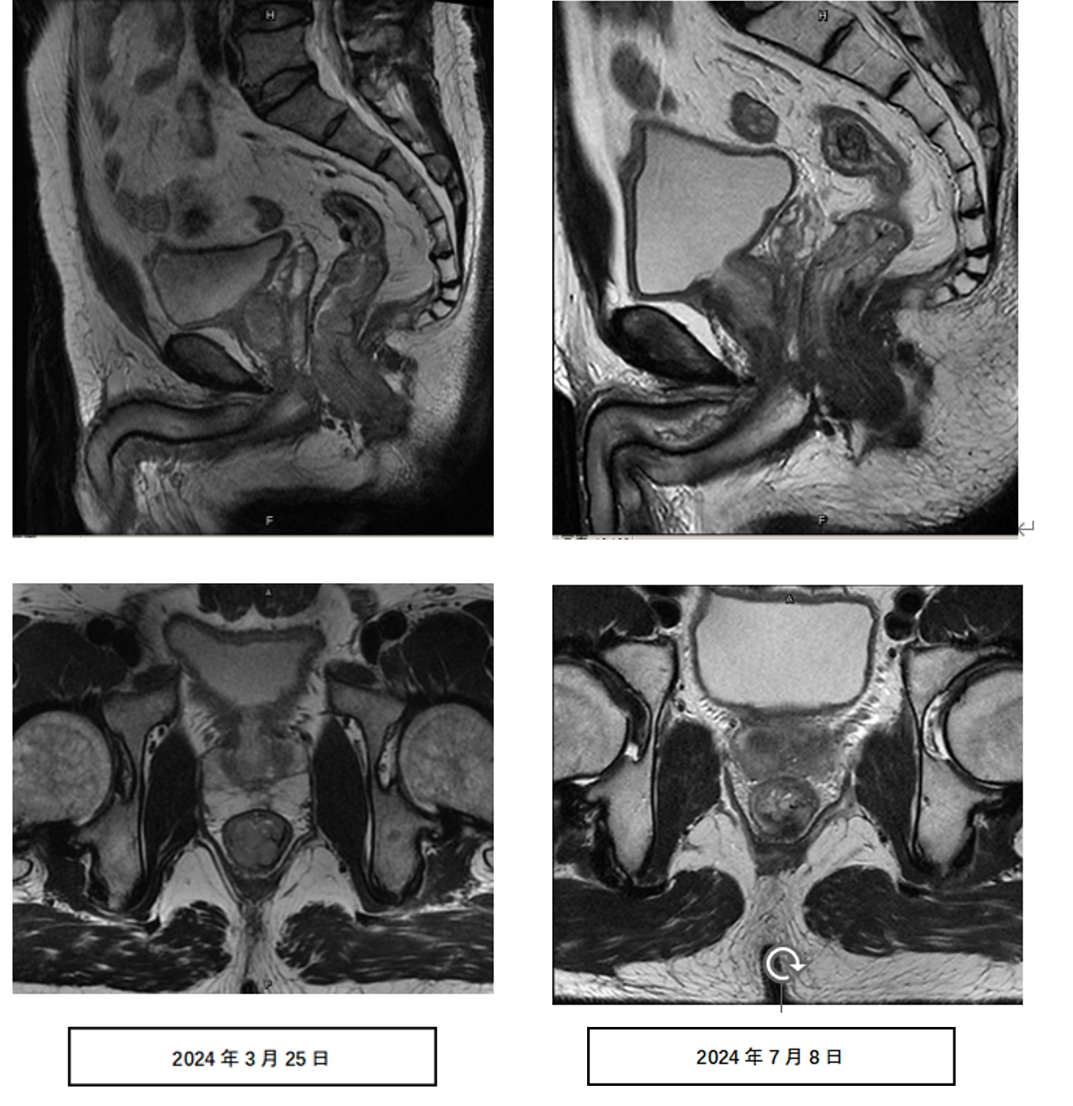

直肠MRI:病变部位:直肠下段,距肛管直肠环约1.2cm;距肛缘约3.2cm;范围受累肠管长度约0.7cm,肠壁最厚处约1.4cm,累及直肠环周1/4,主要累及后壁;T分期:T2,后壁部分可疑侵及肌层;N分期:直肠系膜筋膜内可见多发小淋巴结,较大者短径约0.4cm。MRF(-)。

检查诊断:超低位直肠癌治疗后改变,病灶部分较前黏液化、纤维化,范围较前缩小,请结合临床及相关检查。

治疗前后直肠MRI: